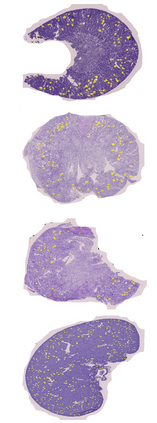

In digital pathology, the traditional method for deep learning-based image segmentation typically involves a two-stage process: initially segmenting high-resolution whole slide images (WSI) into smaller patches (e.g., 256x256, 512x512, 1024x1024) and subsequently reconstructing them to their original scale. This method often struggles to capture the complex details and vast scope of WSIs. In this paper, we propose the holistic histopathology (HoloHisto) segmentation method to achieve end-to-end segmentation on gigapixel WSIs, whose maximum resolution is above 80,000$\times$70,000 pixels. HoloHisto fundamentally shifts the paradigm of WSI segmentation to an end-to-end learning fashion with 1) a large (4K) resolution base patch for elevated visual information inclusion and efficient processing, and 2) a novel sequential tokenization mechanism to properly model the contextual relationships and efficiently model the rich information from the 4K input. To our best knowledge, HoloHisto presents the first holistic approach for gigapixel resolution WSI segmentation, supporting direct I/O of complete WSI and their corresponding gigapixel masks. Under the HoloHisto platform, we unveil a random 4K sampler that transcends ultra-high resolution, delivering 31 and 10 times more pixels than standard 2D and 3D patches, respectively, for advancing computational capabilities. To facilitate efficient 4K resolution dense prediction, we leverage sequential tokenization, utilizing a pre-trained image tokenizer to group image features into a discrete token grid. To assess the performance, our team curated a new kidney pathology image segmentation (KPIs) dataset with WSI-level glomeruli segmentation from whole mouse kidneys. From the results, HoloHisto-4K delivers remarkable performance gains over previous state-of-the-art models.